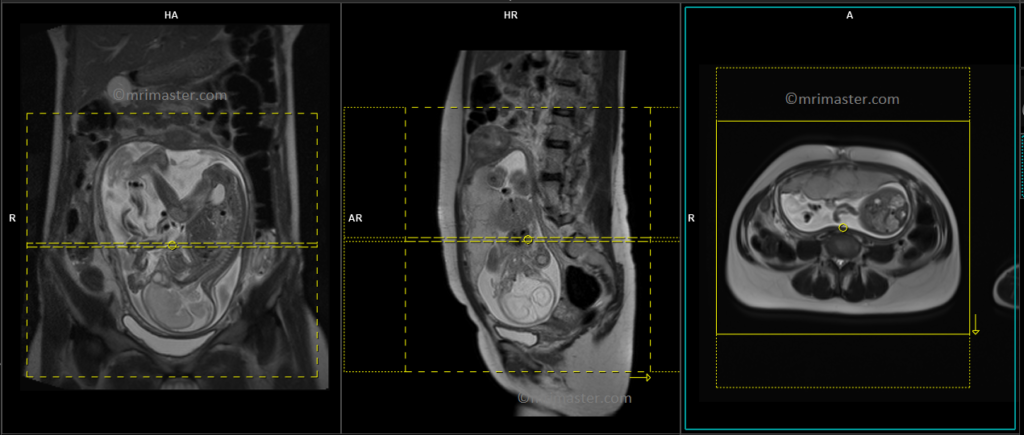

T2 HASTE sagittal 6 mm Respiratory gated

Begin by planning the sagittal slices on the coronal localizer and position the block parallel to the gravid uterus. Verify the positioning block in the other two planes to confirm proper alignment. It is essential to provide an appropriate angle in the axial plane, which should be perpendicular to the gravid uterus. The number of slices should be sufficient to cover the entire abdomen and pelvis, from right to left. The field of view (FOV) must be wide enough to encompass the whole abdomen and pelvis, typically ranging from 400 mm to 480 mm. However, it is important to note that these scans usually take approximately 35 to 40 seconds, which can be challenging for a pregnant woman to hold her breath. To address this issue, we perform the scan under respiratory gating. There are two options for respiratory gating: the liver dome method or the table respiratory sensors. In our department, we utilize the table respiratory sensor.

T2 HASTE coronal 6 mm Respiratory gated

Plan the coronal slices on the sagittal localizer and position the block parallel to the gravid uterus. Verify the positioning block in the other two planes for proper alignment. An appropriate angle should be set in the axial plane, running parallel across the gravid uterus. The number of slices should be sufficient to cover the entire abdomen and pelvis, from the anterior abdominal wall to the spinous process of the vertebrae. The field of view (FOV) must be large enough to encompass the entire abdomen and pelvis, typically ranging from 400 mm to 480 mm. However, it is important to note that these scans usually take approximately 30 to 35 seconds, which can be challenging for a pregnant woman to hold her breath. To address this issue, we perform the scan under respiratory gating. There are two options for respiratory gating: the liver dome method or the table respiratory sensors. In our department, we utilize the table respiratory sensor.

T2 HASTE axial 6 mm Respiratory gated

Plan the axial slices on the sagittal scans and angle the position block perpendicular through the gravid uterus. Verify the positioning block in the other two planes for proper alignment. An appropriate angle should be set in the coronal plane, running perpendicular across the gravid uterus. The number of slices should be sufficient to cover the entire abdomen and pelvis, from the diaphragm to the pubic symphysis. The field of view (FOV) must be large enough to encompass the entire abdomen and pelvis, typically ranging from 400 mm to 480 mm. However, it is important to note that these scans usually take approximately 40 to 45 seconds, which can be challenging for a pregnant woman to hold her breath. To address this issue, we perform the scan under respiratory gating. There are two options for respiratory gating: the liver dome method or the table respiratory sensors. In our department, we utilize the table respiratory sensor.